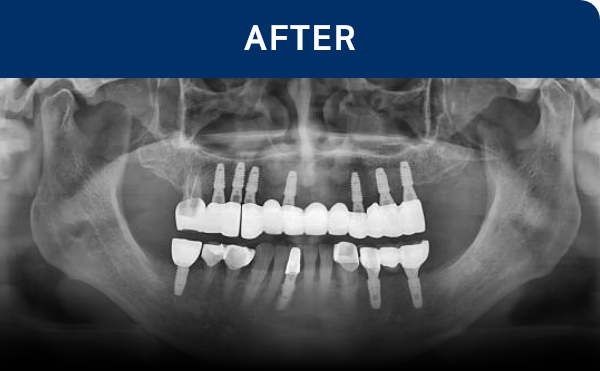

전후가 명확한 결과, 그 결과가

곧 신길플란트치과의 신뢰입니다.

불편함 없이 웃고, 걱정 없이 드실 수 있도록 임플란트로 일상의 편안함을 되찾아드리겠습니다.